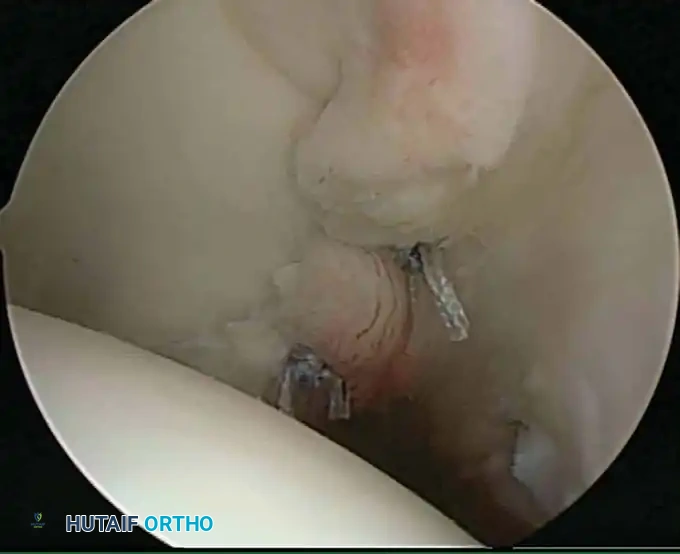

Once diagnostic evaluation is complete and hemostasis is secured, the therapeutic phase commences. Whether performing a SLAP repair, a Bankart stabilization, or a rotator cuff repair, the principles of tissue mobilization, anatomical footprint restoration, and secure biomechanical fixation remain paramount.

Modern arthroscopy relies heavily on suture anchors (biocomposite or all-suture constructs) and advanced arthroscopic knot-tying or knotless techniques. The ability to pass sutures through retracted, fibrotic tissue and secure them under appropriate tension without strangulating the microvascular supply is the hallmark of a master arthroscopist.